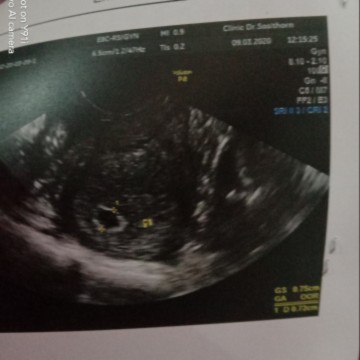

แม่ๆเห็นน้องกี่วิคคะ

วันนี้ไปฝากท้องได้7วิคแล้วคะเห็นถุงน้ำค่ำแล้วแต่งยังไม่เห็นตัวหมอนัดชาวท์อีก2สัปดาห์มาดูอีกที

เจอน้อง8วีคค่ะ